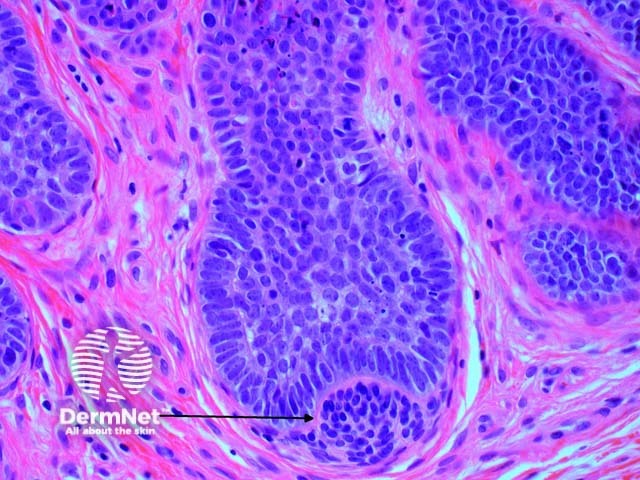

Scanning power view reveals a tumour comprised of multiple nodules situated within the dermis (Figure 1). Small horn cysts, abortive hair follicles and calcification are frequently seen (Figure 2). The stroma is denser and more cellular than with basal cell carcinoma, and there is often focal stromal cracking (Figure 2, arrow). Often pronounced bulbar differentiation may be seen, emulating the follicular bulb and papilla; these structures have been referred to as papillary mesenchymal bodies. (Figure 3, arrow).

Figure 2